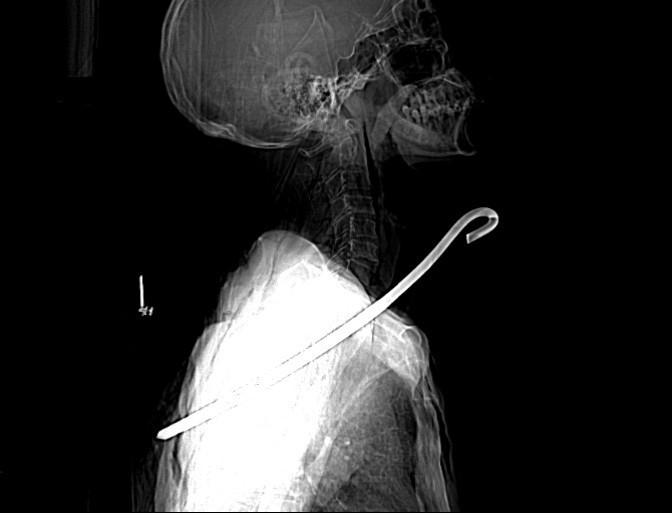

Kết quả chụp CT-Scan cho thấy, dị vật kim loại đường kính 0,8 cm dài khoảng 30 cm xuyên từ vùng cổ phải qua phổi phải và trung thất xuống vùng ngực bên trái gây tổn thương rách thùy trên phổi phải, tràn khí màng phổi trái, tràn khí dưới da thành ngực và vùng cổ; gãy cung sau xương sườn số 5, 6 bên trái, gãy xương bả vai trái…

| Hình ảnh chụp CT-Scan cho thấy thanh sắt xuyên qua cổ ông Đ. ra sau lưng. |